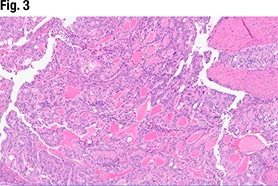

Another part of the tumor (Fig. 3) did show glandular formations, she said, noting that scattered throughout the image are glandular lumens filled with eosinophilic secretions. “The glands themselves are close to pseudostratified in appearance—variable size in the nuclei but not wildly pleomorphic,” she said, and without significant mitotic activity. “Very back-to-back, not seeing very much intervening stroma. So based on this morphology it looks like an endometrioid tumor that is pretty much all gland forming.” But in other areas (Fig. 4), “we see much more solid morphology—it’s not forming glands, it’s not forming papillary structures, it’s very monotonous in appearance,” and it has a high nucleus-to-cytoplasmic ratio. “We do get a sense that there’s mitotic activity,” she said. “So very high grade, very solid. This is not forming any glands at all.”